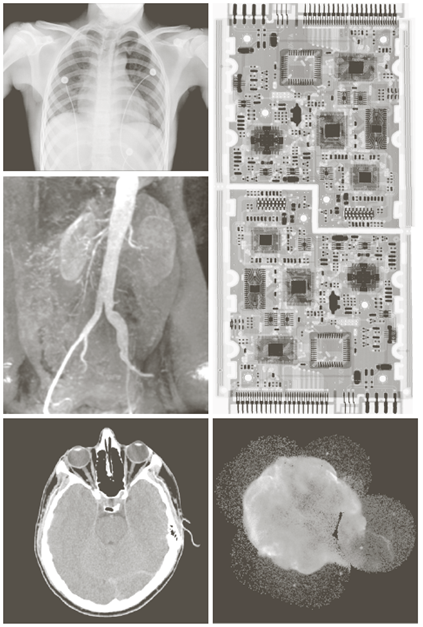

X-ray image

• X선의 투과성을 이용

Image

a) 항암제 Taxol b) 콜레스테롤 c) 마이크로프로세서

Visual band image – 영상처리에 의한 품질검사

a) 회로 기판 b) 포장 알약 c) 병 d) 플라스틱 표면의 기포 e) 씨리얼 f) 각막 이식